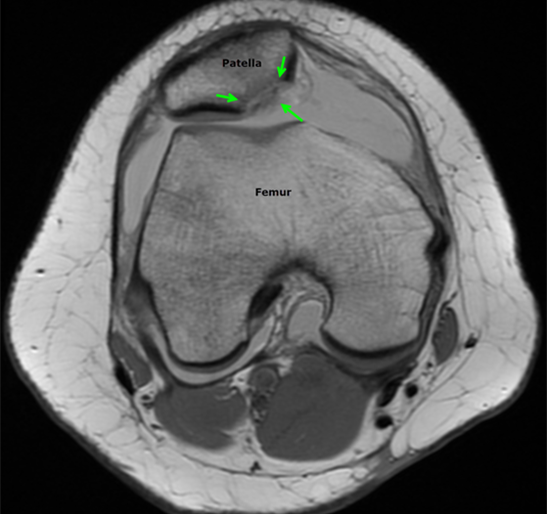

The diagnosis is typically made by history and physical examination. Knee x-rays are obtained initially to look for bone injuries, but cannot fully show the extent of soft tissue damage. For this reason, an MRI is performed soon after to assess the ligaments and cartilage and help determine whether surgery will be necessary. The MRI will also show underlying anatomical features that may predispose to the instability of the patella. If there is a significant injury to the cartilage covering the bone, a loose fragment in the joint, or tearing of the main ligament that stabilizes the patella, surgical treatment is recommended.

Luckily for Patrick Mahomes, the MRI did not show damage to the cartilage or ligaments. He was treated medically with physical therapy and able to return to play in a couple of weeks. The child with the MRI below was not as fortunate and required surgery to repair the patella. After a patellar dislocation, there is an increased risk of a recurrent dislocation, so continued follow-up and therapy are necessary.